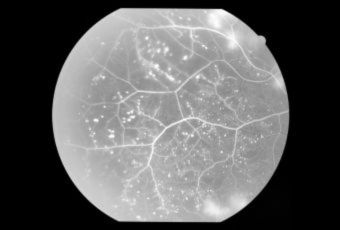

CENTRAL RETINAL VEIN OCCLUSION (CRVO) |

Confluent hemorrhages are the most prominent ophthalmoscopic feature of an acute ischemic central retinal vein occlusion These hemorrhages occur in a wide variety of shapes and sizes; they are usually concentrated in the posterior pole, but may be seen throughout the retina. Many hemorrhages are flame shaped, reflecting the orientation of the nerve fibers. Dot and punctate hemorrhages are interspersed and indicate involvement of the deeper retinal layers. Bleeding may be extensive, erupting through the internal limiting membrane to form a preretinal hemorrhage or extending into the vitreous. Small dot hemorrhages may be seen either isolated or clustered around small venules. The entire venous tree is tortuous, engorged, dilated, and dark. The retina is edematous, particularly in the posterior pole; some of this edema may obscure portions of the retinal vessels. Cotton-wool patches (soft exudates) are often present. The disc margin is blurred or obscured, and the precapillary arterioles appear engorged. Splinter hemorrhages and edema are present on the disc surface and extend into the surrounding retina. The physiologic cup is filled, and the venous pulse is absent. The arterioles, often overlooked because of the other more striking pathologic features, are frequently narrowed. Sometimes in central retinal vein occlusion of acute onset, the fundus picture is less dramatic, and all of the findings previously discussed may be present, but to a lesser degree. Vision depends on extent of macular involvement